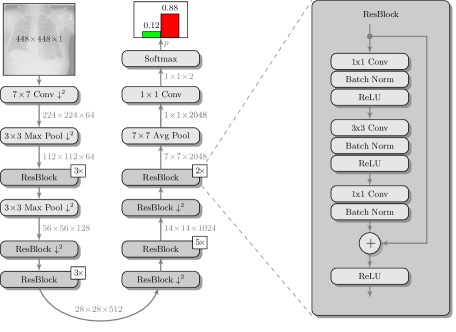

In the following method, a specific network architecture - a residual network - is employed. We use a variant of the ResNet-50 architecture [5] with a single input channel and an enlarged input size of , which allows to leverage the higher spatial resolution of X-ray data, e.g. for the detection of small structures [1]. Therefore, an additional pooling layer was introduced after the first bottleneck block (cf. Fig. 1). The network was trained on the NIH ChestX-ray14 dataset [10] to predict 14 pathologies. For the task of pneumothorax detection, the dense layer for the prediction of pathologies was replaced by a new layer for binary classification.

Fig. 2 shows a schematic of the proposed architecture. In this architecture, we use the previously discussed ResNet-50 network as patch classifier.